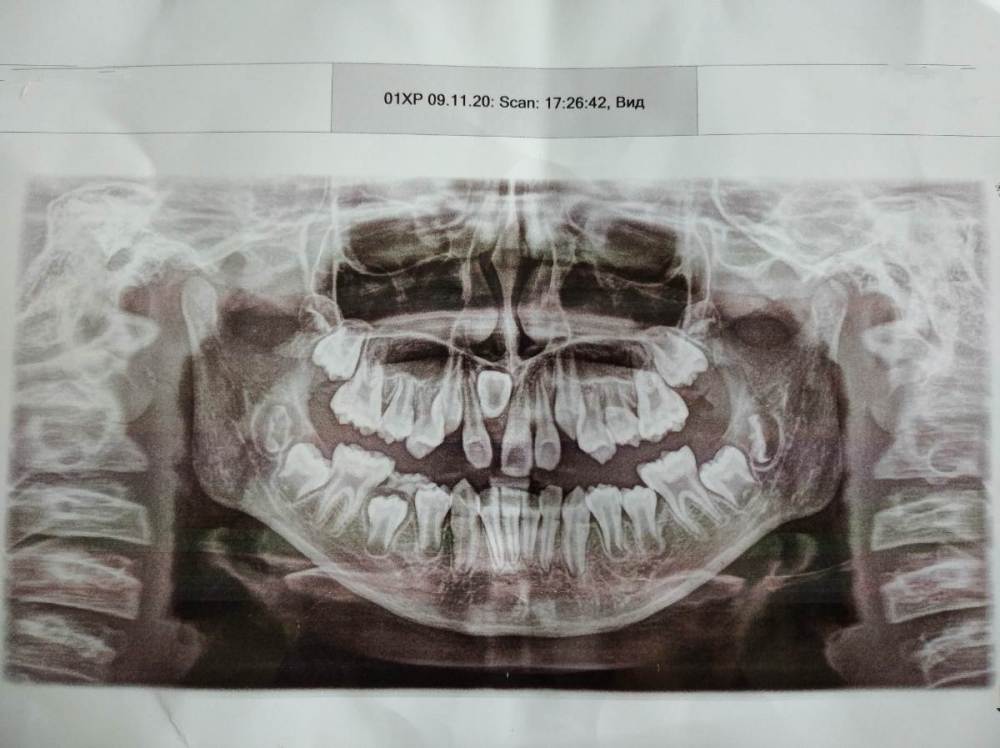

Kri_ssty Опубликовано 13 июня, 2021 Поделиться Опубликовано 13 июня, 2021 пожалуйста, подскажите, что это такое и что можно сделать? ребенку 11 лет. Ссылка на комментарий

red_butler Опубликовано 14 июня, 2021 Поделиться Опубликовано 14 июня, 2021 нужно сделать Кт и сходить к ортодонту 2 Ссылка на комментарий